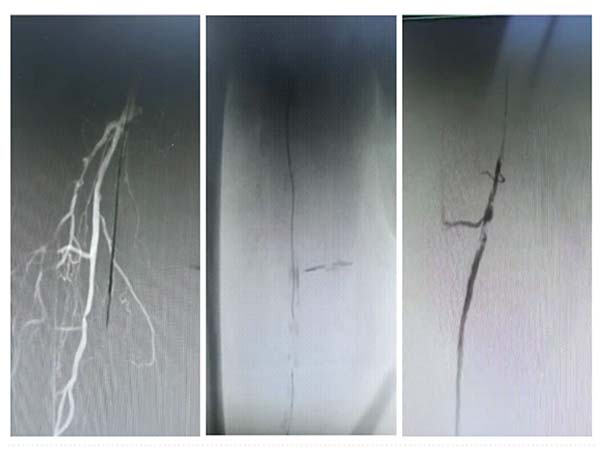

手术效果立竿见影。术后造影清晰显示,患者闭塞的下肢动脉彻底打通,血运恢复通畅,缺血症状当即缓解。术后患者下肢疼痛快速减轻,皮温明显回升,足背动脉搏动恢复,经后续治疗已能轻松行走数百米。